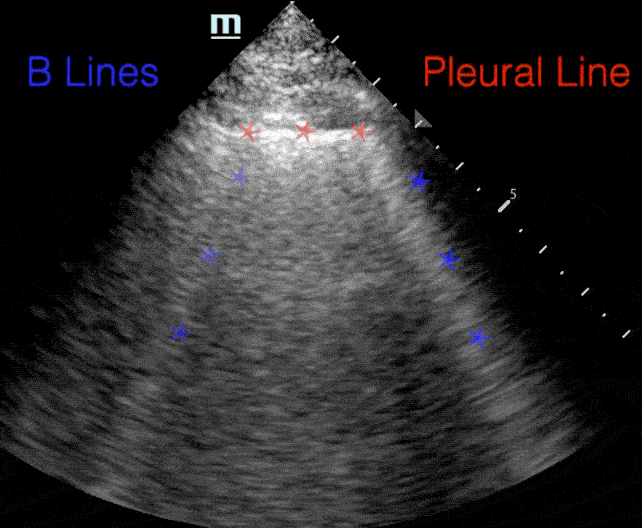

A lines:

• Horizontal repetitions of the pleural lines

B lines:

• Comet tail artifact

• Arise from pleura

• Move with respirations

• Erase A-lines

• Artifact generated in alveolar-interstitial syndromes

• Etiology depends on associated features and whether they are focal or bilateral

B-lines